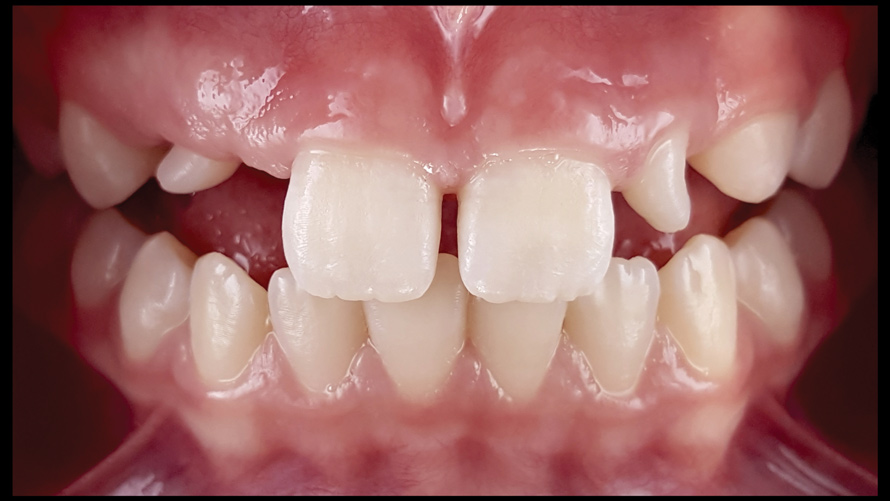

(9. through 11.) Preoperative esthetic case documentation using a smartphone and an EALS device.

Figure 9

Figure 10

Figure 11

One of the main advantages that smartphone cameras have over DSLR cameras is that nearly everyone is already very familiar with the technology; therefore, the incorporation of these devices into everyday practice does not require learning a new and unfamiliar skill set. The task of producing a series of high-quality clinical photographs for routine examinations (Figure 8), esthetic treatment planning (Figure 9 through Figure 11), or specialty care (Figure 12 and Figure 13) can be delegated with confidence to any staff member during the patient's initial office visit and will generally require less than 5 minutes of time to complete. When a DSLR camera is used, evaluation of the intraoral images either takes place on the small viewfinder built into the camera or necessitates the physical removal of the memory card from the camera to downloaded the images onto a computer for review. An added bonus of smartphone dental photography is that the phone's screen now replaces the much smaller viewfinder of a DSLR camera and provides the clinician with the ability to view and zoom into the patient images on a 5- to 6-inch, high-definition display.